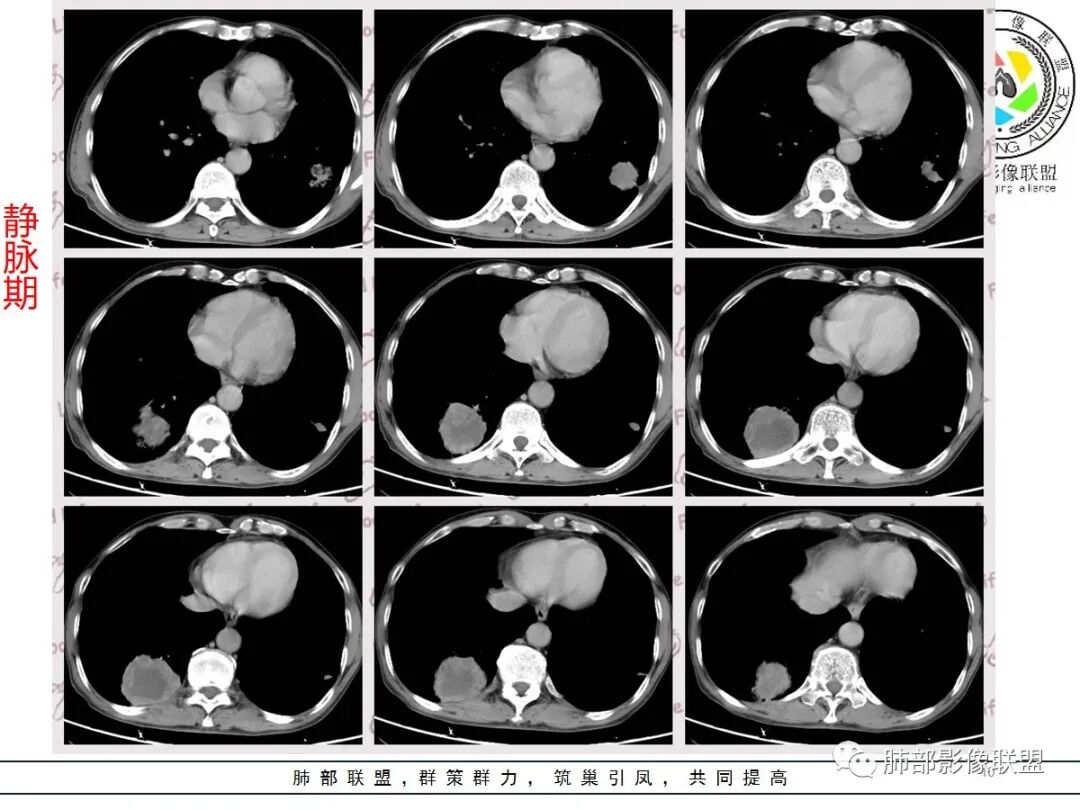

右下肺穿刺,病理科医生考虑癌肉瘤,两种成分!

病理科老师当时来我们科讨论,就是有鳞癌和肉瘤两种成分呢,应该就是我们说的癌肉瘤或者肉瘤样癌一类

南边:

今天晨读我觉得最有特征性的就是那个强化,环状强化,周围强化比较明显的是癌,血供丰富,中间应该是肉瘤粘液变性,而且边界比较清楚,这个也算肉瘤样癌比较有特征性的,其他的跟其他恶性确实不好鉴别

主要征象:病灶分叶不明显、较光整,局部胸膜栽赃,支气管门口堵塞,有推移迹象;增强后坏死明显,内部囊变坏死边缘部分清楚、部分不清楚,病灶内可见血管,局部稍毛糙,实性部分强化较明显,总体考虑恶性病变。一部分征象指向鳞癌(支气管截断、坏死较多,病灶内血管破坏),但又有肉瘤的一些特点(病灶较大,缺乏分叶,坏死边界清晰),要考虑到肉瘤样癌。

二、原发性肺肉瘤样癌(PSC)

1、2004版定义肉瘤样癌为一类分化差的非小细胞癌,包括5个亚型(多形性癌、梭形细胞癌、巨细胞癌、癌肉瘤和肺母细胞瘤),2015版将多形性癌、梭形细胞癌和巨细胞癌独立出来,归于一个章节,癌肉瘤及肺母细胞瘤各归为独立章节,可能从侧面反映了3类肿瘤在发生部位、发病人群及组织形态和分子遗传学方面确有不同。目前组织学研究认为,PSC是一组起源于相同原始上皮、经上皮-间质转化(EMT)后形成的一组转化性癌。肿瘤恶性程度高,易发生转移,预后较差。主要治疗措施为手术切除。

2、本例最后病理考虑多形性癌(PC),PC是一类分化差的含有梭形细胞和/或巨细胞或只由梭形或巨细胞成分组成的非小细胞癌。对多形性癌仍要求肿瘤性梭形细胞和/或巨细胞至少占10%,小活检或细胞标本中可描述肉瘤样成分,不要求做出确切的诊断。

3、本病好发于60岁以上的老年男性,多数有吸烟史。周围型多于中央型,病灶边缘较清楚,多数光整圆钝,部分可见浅分叶,少数有毛刺,无胸膜凹陷征出现。CT平扫时呈软组织密度,较小的肿块密度较均匀,肿块较大时中央常出现坏死。增强扫描肿块多呈斑片状不均匀强化,而肿瘤周边厚薄不均的囊壁样强化较具特征性。周围型多数位于胸膜下,常常侵犯胸膜或胸壁。